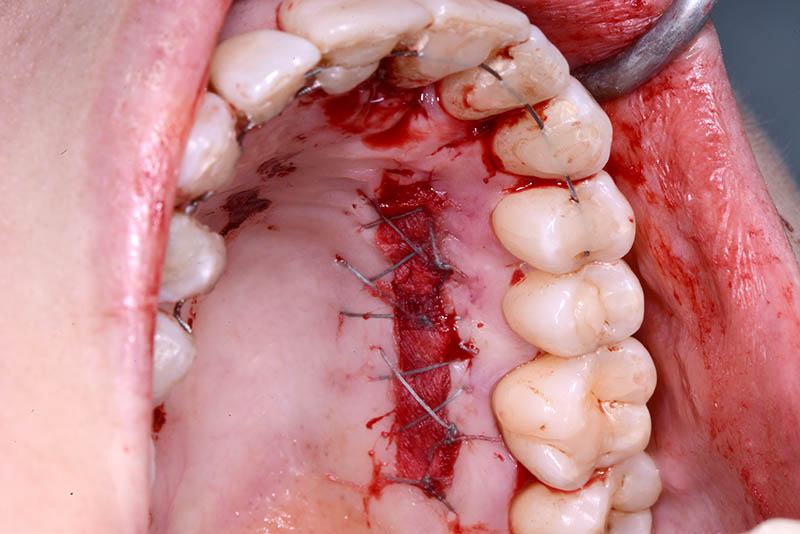

At the end of the orthodontic treatment, a coronally advanced flap was performed according to the De Sanctis and Zucchelli technique, involving papilla preservation and connective tissue grafting, to restore the gingival contour and the papilla between teeth 21 and 22.

connective graft